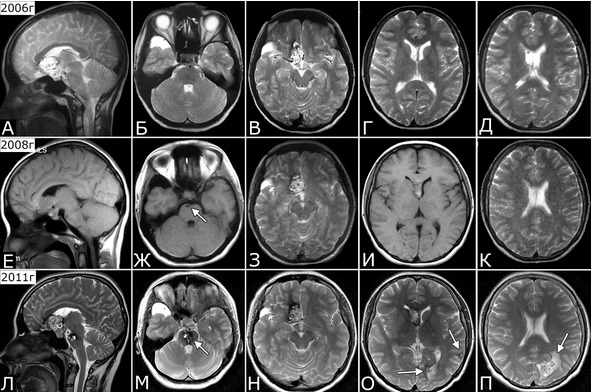

Рис. 31. Б-ная Е-ва, 1985 г. р. Новообразование кавернозных мальформаций. Клинический диагноз: множественные КМ головного мозга

Течение болезни (б-ная Е-ва, 1985 г. р.): 1994 г – клиническая картина САК. Госпитализировна, при ЛП получен кровянистый ликвор. Лечилась с д-зом «гнойный менингит с геморрагическим компонентом». 2000 г. (14 лет) – резкое снижение зрения на OD. При обследовании в офтальмологической клинике выявлена отслойка сетчатки справа, принято решение об операции. С учетом анамнеза, выполнена МРТ головы, при которой выявлена кавернома медиальных отделов лобной доли и передних отделов гипоталамуса справа (22х20х17 мм) и арахноидальная киста полюса правой височной доли. В связи с обнаруженной патологией глазная операция отложена и выполнена только в 2010 г. В 2004 родила дочь. При контрольной МРТ в 2006 г – прежняя патология (А – Д). При контрольной МРТ в 2008 г (23 г) выявлено дополнительное образование в виде небольшой щелевидной полости в основании моста (Ж, стрелка). 8.08.2010 г (25 лет) появилась сильная головная боль, рвота, головокружение, шаткость при ходьбе, неадекватность поведения. Госпитализирована, при МРТ выявлены дополнительные образования в виде гематомы ствола до 2см в диаметре, кавернома левой затылочной доли и микрокавернома субкортикальных отделов левой височной доли. Наличие этих образований подтверждено при МРТ в институте в 2011 г (Л – П, стрелки). При осмотре в институте спустя месяц после кровоизлияния на фоне удовлетворительного общего состояния выявлена рассеянная умеренная стволово-мозжечковая симптоматика, которая полностью регрессировала к моменту осмотра 21.01.2012. Продолжено наблюдение.